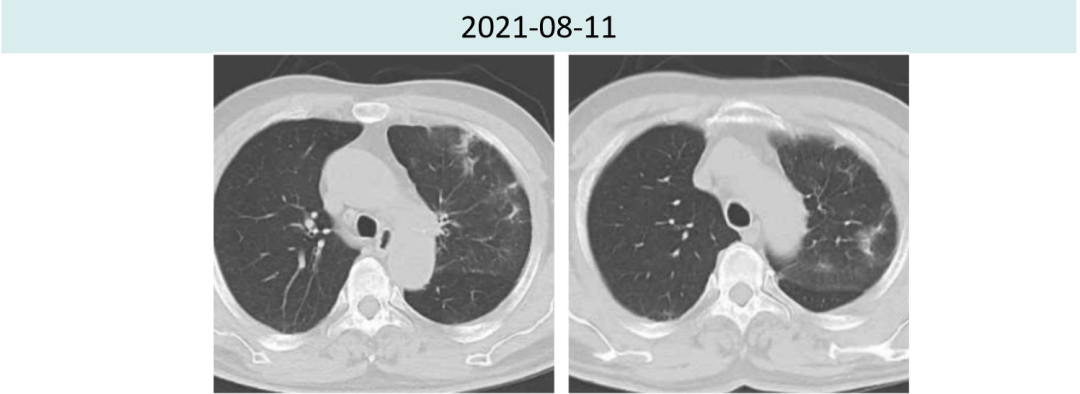

2021年8月11日激素治疗6周后,胸部CT提示两肺炎症较前进?步好转。肿瘤疗效评价持续PR(4.5cm→1.6cm)。

2021年8月11日免疫性肺炎已缓解至≤G1级。

2021年9月26胸部CT提示间质性肺炎较前进?步好转,肿瘤略增大(1.6cm→2.2cm),疗效评价PD。

图2.患者治疗前后肺炎情况对比